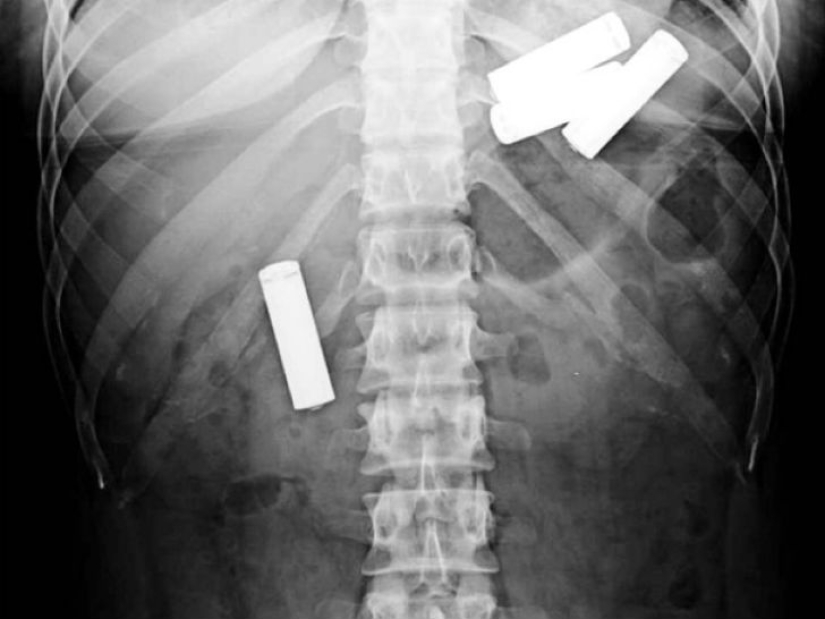

Sí, tragar cubiertos es un placer caro. ¿Qué hay de las 78 cucharas de plata que una mujer de 52 años se tragó en los Países Bajos?